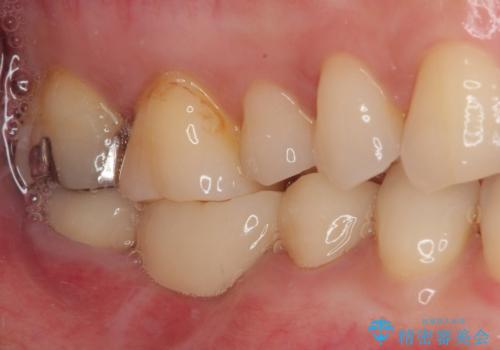

- 奥歯から膿が出てくることを気にして来院された患者様です。

診察より、奥から2番目の歯が割れている可能性が非常に高いため、まずは奥から2番目の歯の状態を診断することとしました。

クラウンを外したところ、目視でも確認できる破折線が認められたため、抜歯することとしました。